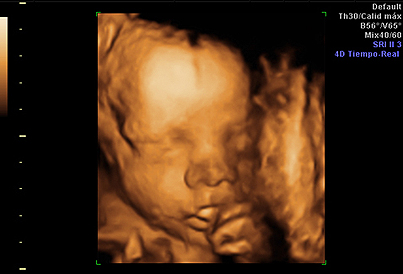

Todas las familias están deseando conocer la carita de su futuro bebé, y hoy en día muchas madres recurren a las ecografías en 4D, que ofrecen imágenes realmente impresionantes. A quién no se le ha caído la baba ante esas pantallas que nos muestran al feto como si ya estuviera fuera… Pero, ¿sabemos en qué consiste esta prueba? Y, si realmente solo existen tres dimensiones, ¿por qué se le llama 4D? A estas preguntas y otras nos contesta Inés Tamarit Degenhardt, especialista en Ginecología y Obstetricia.

Así como una ecografía en dos dimensiones recoge imágenes de cortes o secciones del feto, la de tres dimensiones une cientos de estas secciones para reconstruir la superficie externa del feto. Para que se entienda, es como si unimos todas las rebanadas de una hogaza de pan para obtener su forma original.

Porque a las tres espaciales unimos el tiempo. Es decir, la ecografía 4D consiste en ver imágenes en 3D junto con sus movimientos a tiempo real, de manera que podemos visualizar el exterior del feto moviéndose.

Aunque se puede realizar en cualquier momento, para ver satisfactoriamente la cara fetal es recomendable realizarla alrededor de la semana 28 de la gestación, que es cuando el feto tiene las facciones más parecidas a las de un recién nacido; además, en este momento es cuando se tiene una cantidad óptima de líquido amniótico.